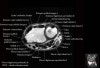

- Coronal section

Coronal T1 imaging evaluates bone marrow signal (ex. increased in avascular necrosis) and the relationship of the osseous structures to each other (ex. scapholunate disassociation).